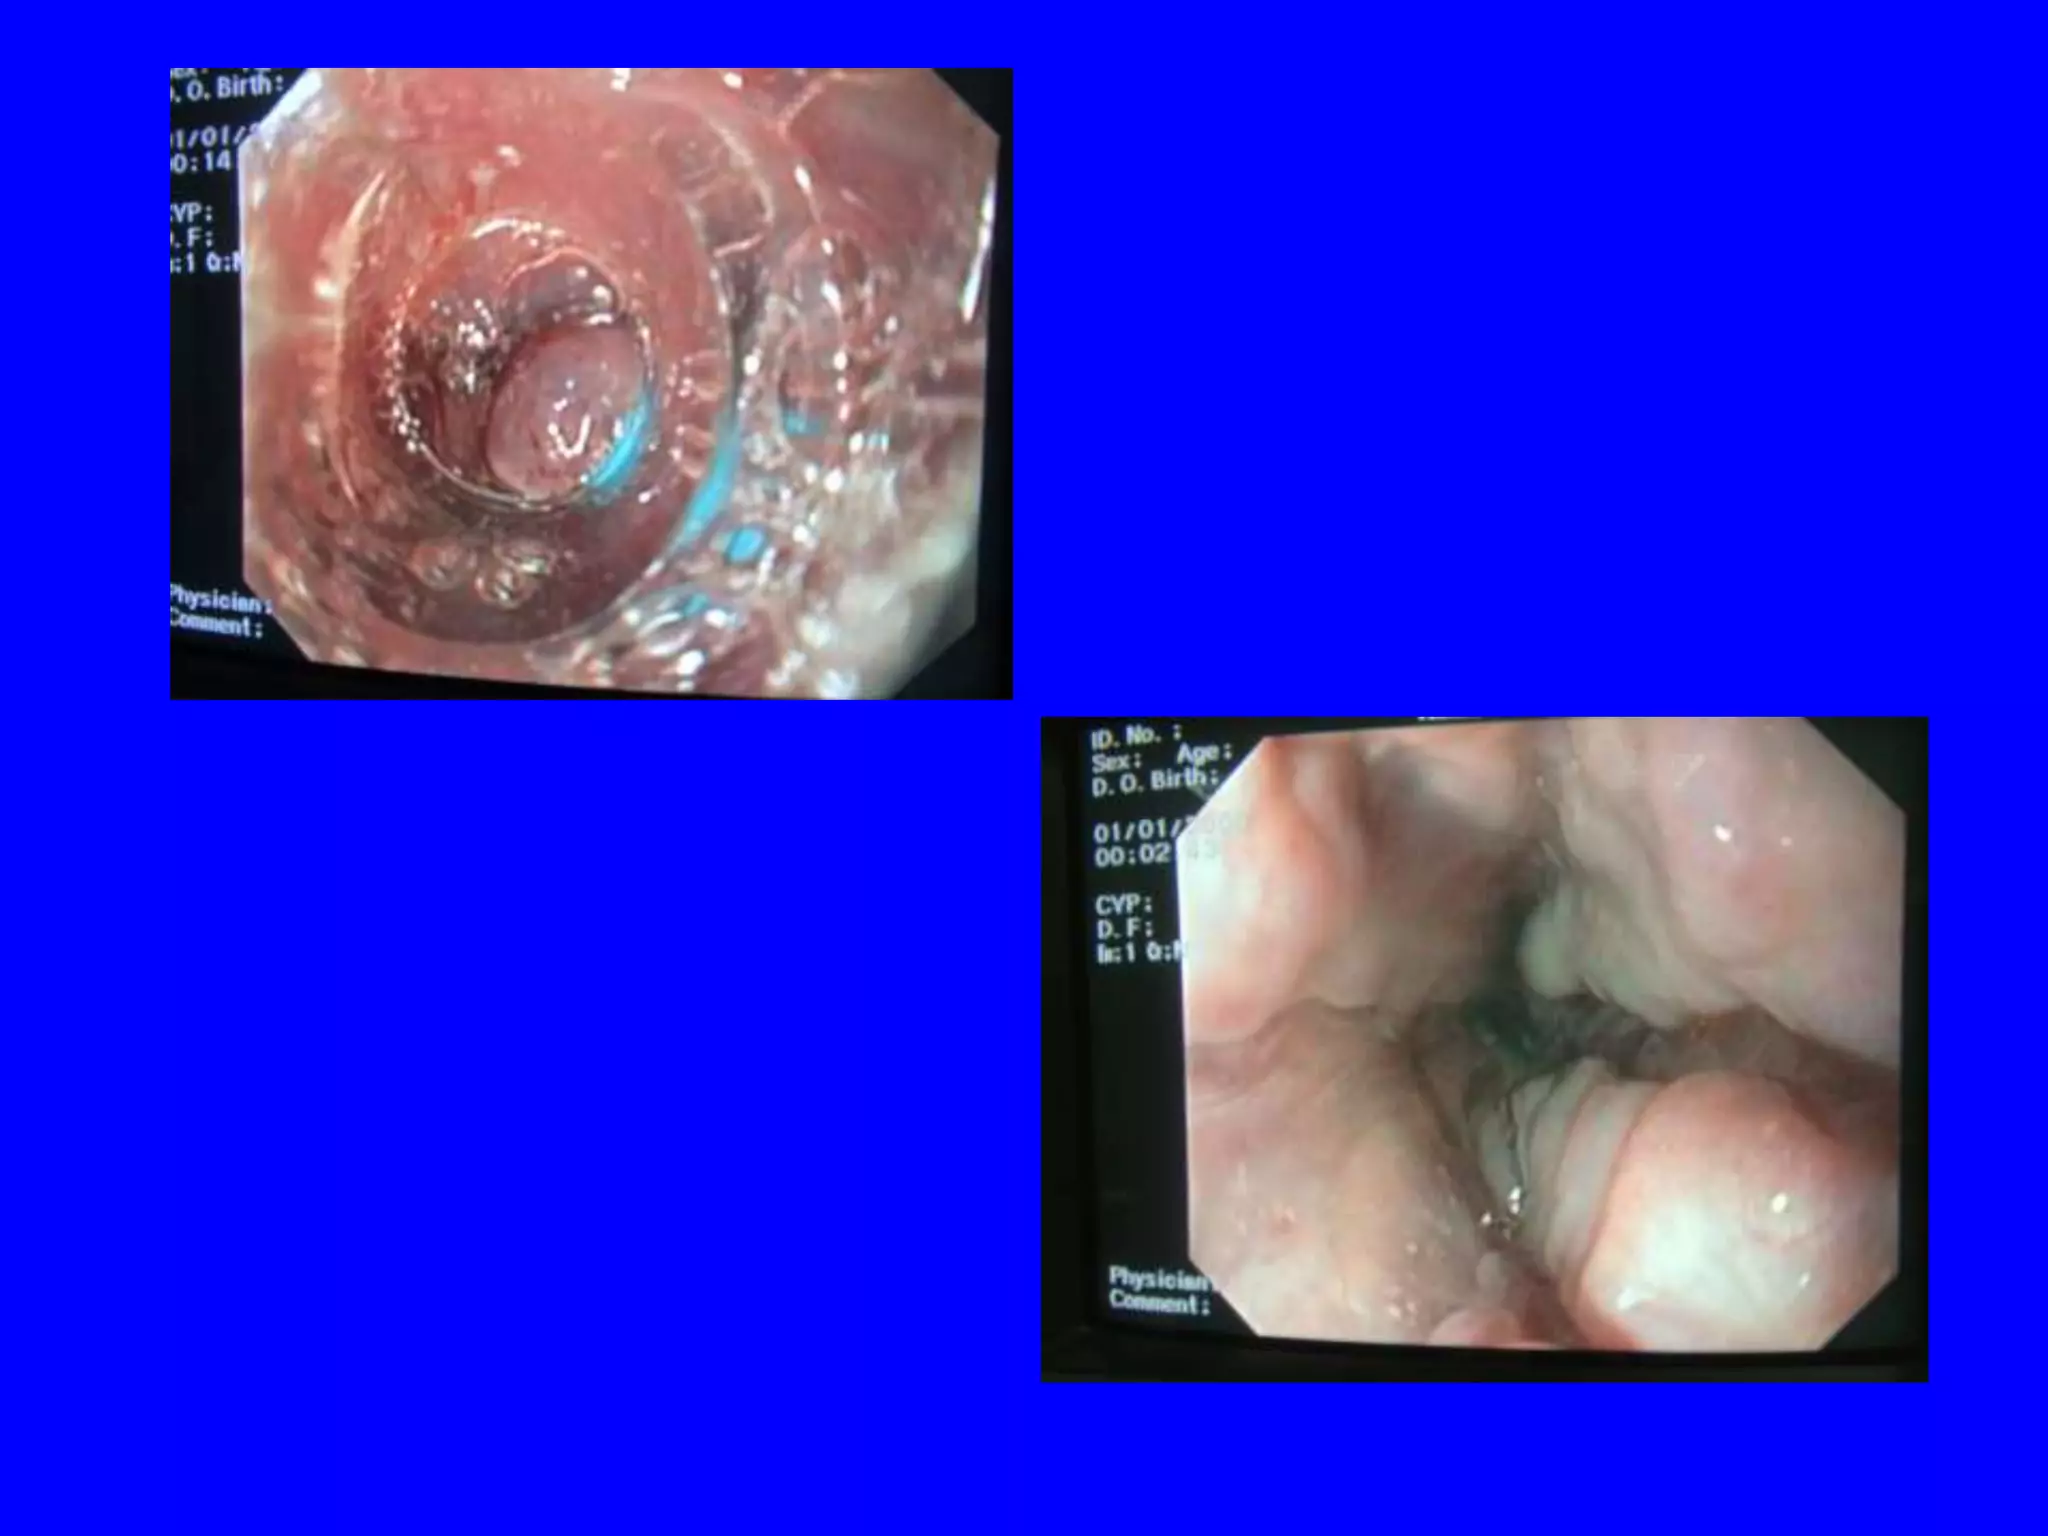

• Endoscopic treatment:

• Low-risk ulcers not requiring endoscopic intervention are clean-

based or have a non-protuberant pigmented spot.

• Intermediate-risk ulcers have adherent clots & should be vigorously

irrigated to dislodge the clot & reclassified based on appearance.

• High-risk ulcers that require endoscopic treatment: active arterial

spurting or a non-bleeding visible vessel &.